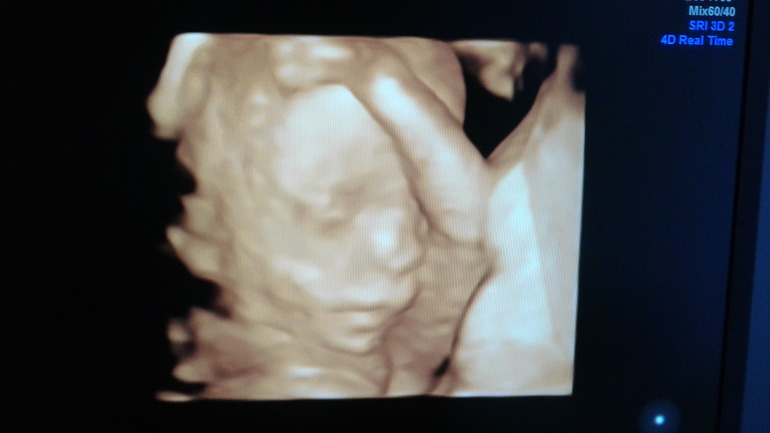

Мальчик, мальчишка, сыночек))))Расти здоровеньким, наш малыш! Мы все тебя любим и ждём!

И мой беременный бледный морской пуз)))). Это уже полная 21 неделя.